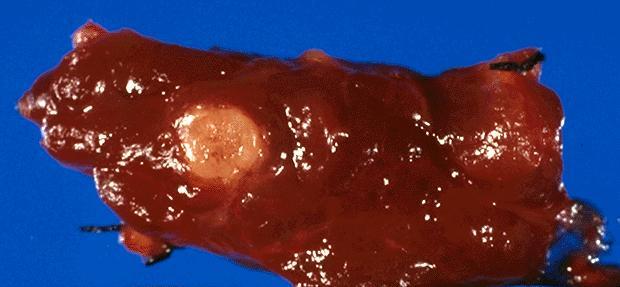

Gross description

- Sporadic: typically presents as a single circumscribed but nonencapsulated, gray-tan mass

- Familial: generally bilateral / multiple foci

- Solid, gray-tan-yellow, firm, may be infiltrative

- Larger lesions have hemorrhage and necrosis, tumor usually in mid or upper portion of gland (with higher density of C cells)

- < 1 cm in size is called microcarcinoma; if < 0.5 cm, associated with a complete absence of clinically detectable metastatic disease (Ann Surg Oncol 2009;16:2875)

Gross images

Contributed by Mark R. Wick, M.D.

AFIP images